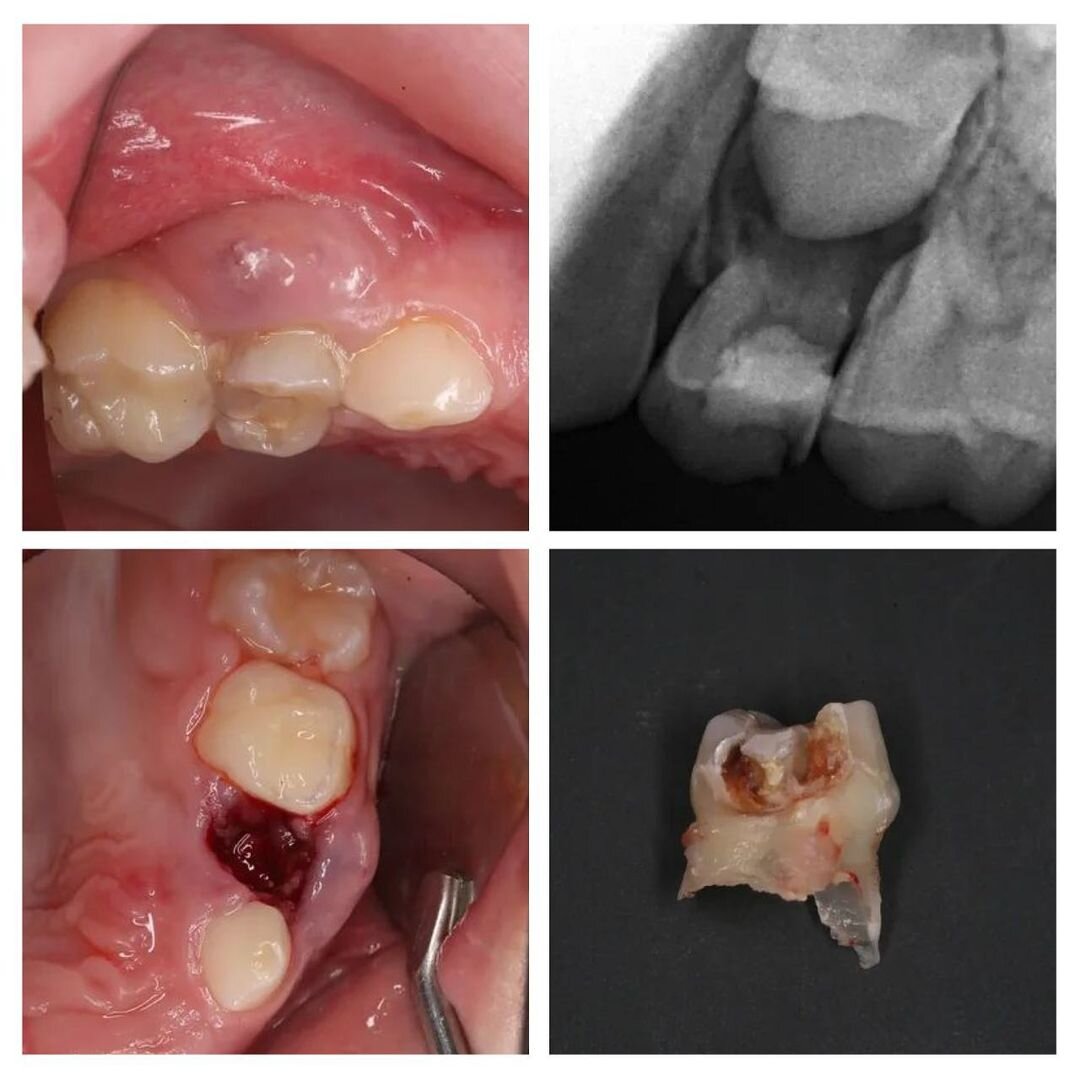

Еще один наглядный пример, что у детей все процессы идут просто молниеносно.

Пациенту 7 лет.

Мама привела его лечить зубы, т.к. «четверка» уже сильно разрушена.

Сделали снимок и что видим: воспаление уже вышло за пределы зуба и поразило периодонт (связочный аппарат, который удерживает зуб на месте).

Это прямое показание к удалению молочного зуба!

Сразу сказала, что нужно удалять, что со дня на день на десне вылезет свищ.

Что вы думаете — СВИЩ❗

Зуб, естественно, удалили.